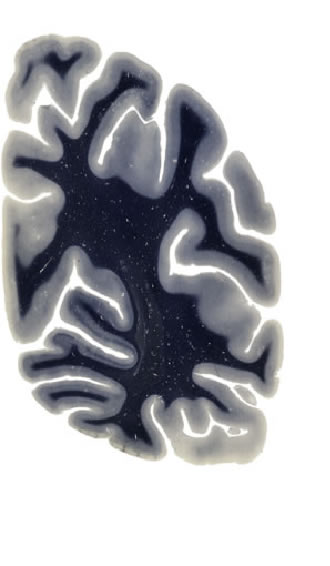

Hi-Resolution Sections · Cells (Nissl Staining) · Virtual Microscopy

Frontal sections (Nissl) from the Atlas Brain:

Macroscopy

Slice ID:

r4-0920

Plate NR:

59

Position:

61,6 mm